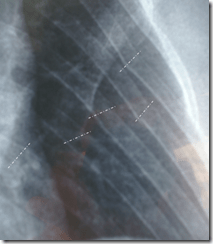

Current estimate is 4 – 5 weeks for my ribs to heal, I have to say it’s pretty painful right now, and I expect it will be for a couple of weeks yet. ![]()